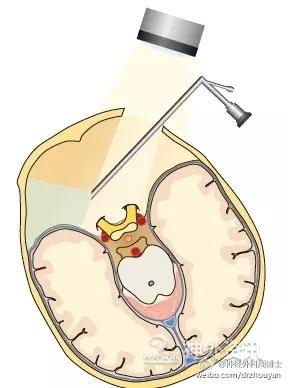

问题 4:术者必须看到解剖结构,这才是最安全的。Keyhole的小骨窗不利于显微镜的光束进入到深部区域。为了解决这个问题,使用神经内镜可以有效的弥补手术显微镜的不足。

神经内镜有三个优点:1. 可使光线强度增高;2. 扩大视野角度;3. 近距离清晰的观察解剖结构的细节。

第一个意识到手术显微镜缺点的是Werner Prott(1974年),当时他正在使用诊断内镜观察桥小脑角池的结构。随后,1977年Michael L. J. Apuzzo介绍了侧视望远镜,1981年Falk Oppel在进行三叉神经显微血管减压术时使用了术中内镜。所有的这些工作都被认为是开创了内镜辅助神经外科的新领域。